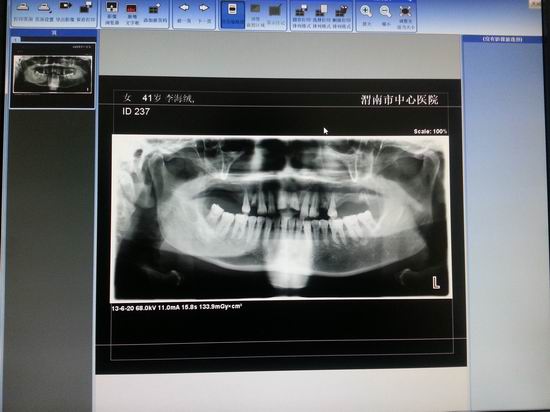

数字化口腔全景X射线机ProMax3D

名称:数字化口腔全景X射线机ProMax3D

主要功能:PLANMECA ProMax 3D系列X线设备为满足现代口腔外科的需要而设计,采用锥形射线束立体断层摄影容(CBCT)扫描技术、三维重建算法、最新的平板探测器技术、SCARA技术、具有频闪效应的短脉冲曝光模式等,以获取病人口腔、副鼻窦乃至整个头颅的精细解剖结构的全部信息, 将原始二维X线投射影像转换为三维容积影像,可采集及其精细的影像,使得机器运动确保准确可靠,完成所要求的任何运动模式,不但提高了影像质量,而且消除了伪影。